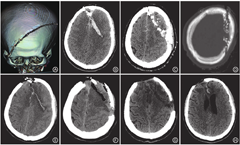

患者男,41岁,因工作时不慎伸手低头取电锯下方物品时,头颅碰到固定且高速转动的电锯被切割。当即意识不清伴大量出血,于伤后0.5 h送达我院就诊,急诊室体检:血压110/72 mmHg(1 mmHg=0.133 kPa),心率74次/min,浅昏迷,躁动,格拉斯哥昏迷评分(GCS)为7分,刺痛能睁眼及屈曲肢体,无发音。右额至左顶部头皮挫裂伤长约26 cm,皮缘挫伤严重并裂开,颅骨粉碎骨折外露,呈窄条状颅骨缺损,并有破碎脑组织向外溢出,创面渗血伴有大量头发屑、骨碎片附着。双侧瞳孔直径均0.25 cm,光反射灵敏,四肢刺痛能屈曲。急诊采用大敷料头部加压包扎、建立静脉输液通道等处理后行头颅+颈椎+胸部CT检查。头颅CT检查示:双侧额骨及左侧顶骨穿通性骨折伴骨质缺损,部分碎骨片嵌入颅内,双侧额叶脑挫裂伤,蛛网膜下腔出血(图1A~D)。查血常规示:血红蛋白125 g/L,红细胞压积0.36。临床诊断:特重型开放性颅脑损伤,双侧额骨及左侧顶骨穿通性骨折伴双额叶脑挫裂伤,上矢状窦前1/3断裂,蛛网膜下腔出血。急诊做好常规术前准备后行开放性颅脑损伤清创术。术前备皮时出血量多,血压下降至88/60 mmHg,加快输液速度,即送手术室。

手术过程:术前抗生素罗氏芬(头孢曲松)针2 g静脉滴注,德巴金针0.4 g静脉微泵注。气管插管全身麻醉后,监测血压为70/50 mmHg,予加用去甲肾上腺素针微泵维持血压回升至约100/70 mmHg。取仰卧位,常规消毒铺巾,清创去除头发屑及骨碎片,修剪皮缘,止血,再大量生理盐水冲洗;重新二次消毒铺巾,沿原创口皮缘撑开,两侧骨膜下剥离部分骨膜,于近上矢状窦处钻两孔,铣刀游离骨瓣,形成6 cm×24 cm骨窗,见上矢状窦已离断并活动性出血予以结扎。硬脑膜破碎裂开,其下张力高,有大量小碎骨片及头发屑嵌入脑组织中,予以清除破碎骨片及头发屑,清创双侧额顶叶切割的脑挫裂伤破碎脑组织并清除右额叶脑内血肿约40 ml,见右胼缘动脉分支断裂出血汹涌,予电凝止血,残腔严密电凝止血,彻底清创后脑压明显下降,但仍呈轻度膨出,脑搏动良好。创面大量生理盐水反复冲洗。取人工脑膜(北京天义福公司)充分减张修补硬脑膜缺损,硬脑膜外腔过氧化氢、生理盐水反复冲洗,硬脑膜外置一负压引流管,骨瓣去弃,逐层缝合头皮,术毕。术中出血约1 000 ml,输红细胞悬液8 U,血浆1 000 ml,术中血压一直靠升压药(去甲肾上腺素针)才维持正常水平。术中追加罗氏芬针2 g。术后行中心静脉压监测、动态CT复查(图1E~H)、止血抗炎(罗氏芬针2 g/d)及抗癫痫、脱水等综合治疗。